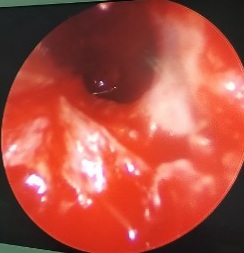

Lổ thông xoang bướm sau phẫu thuật